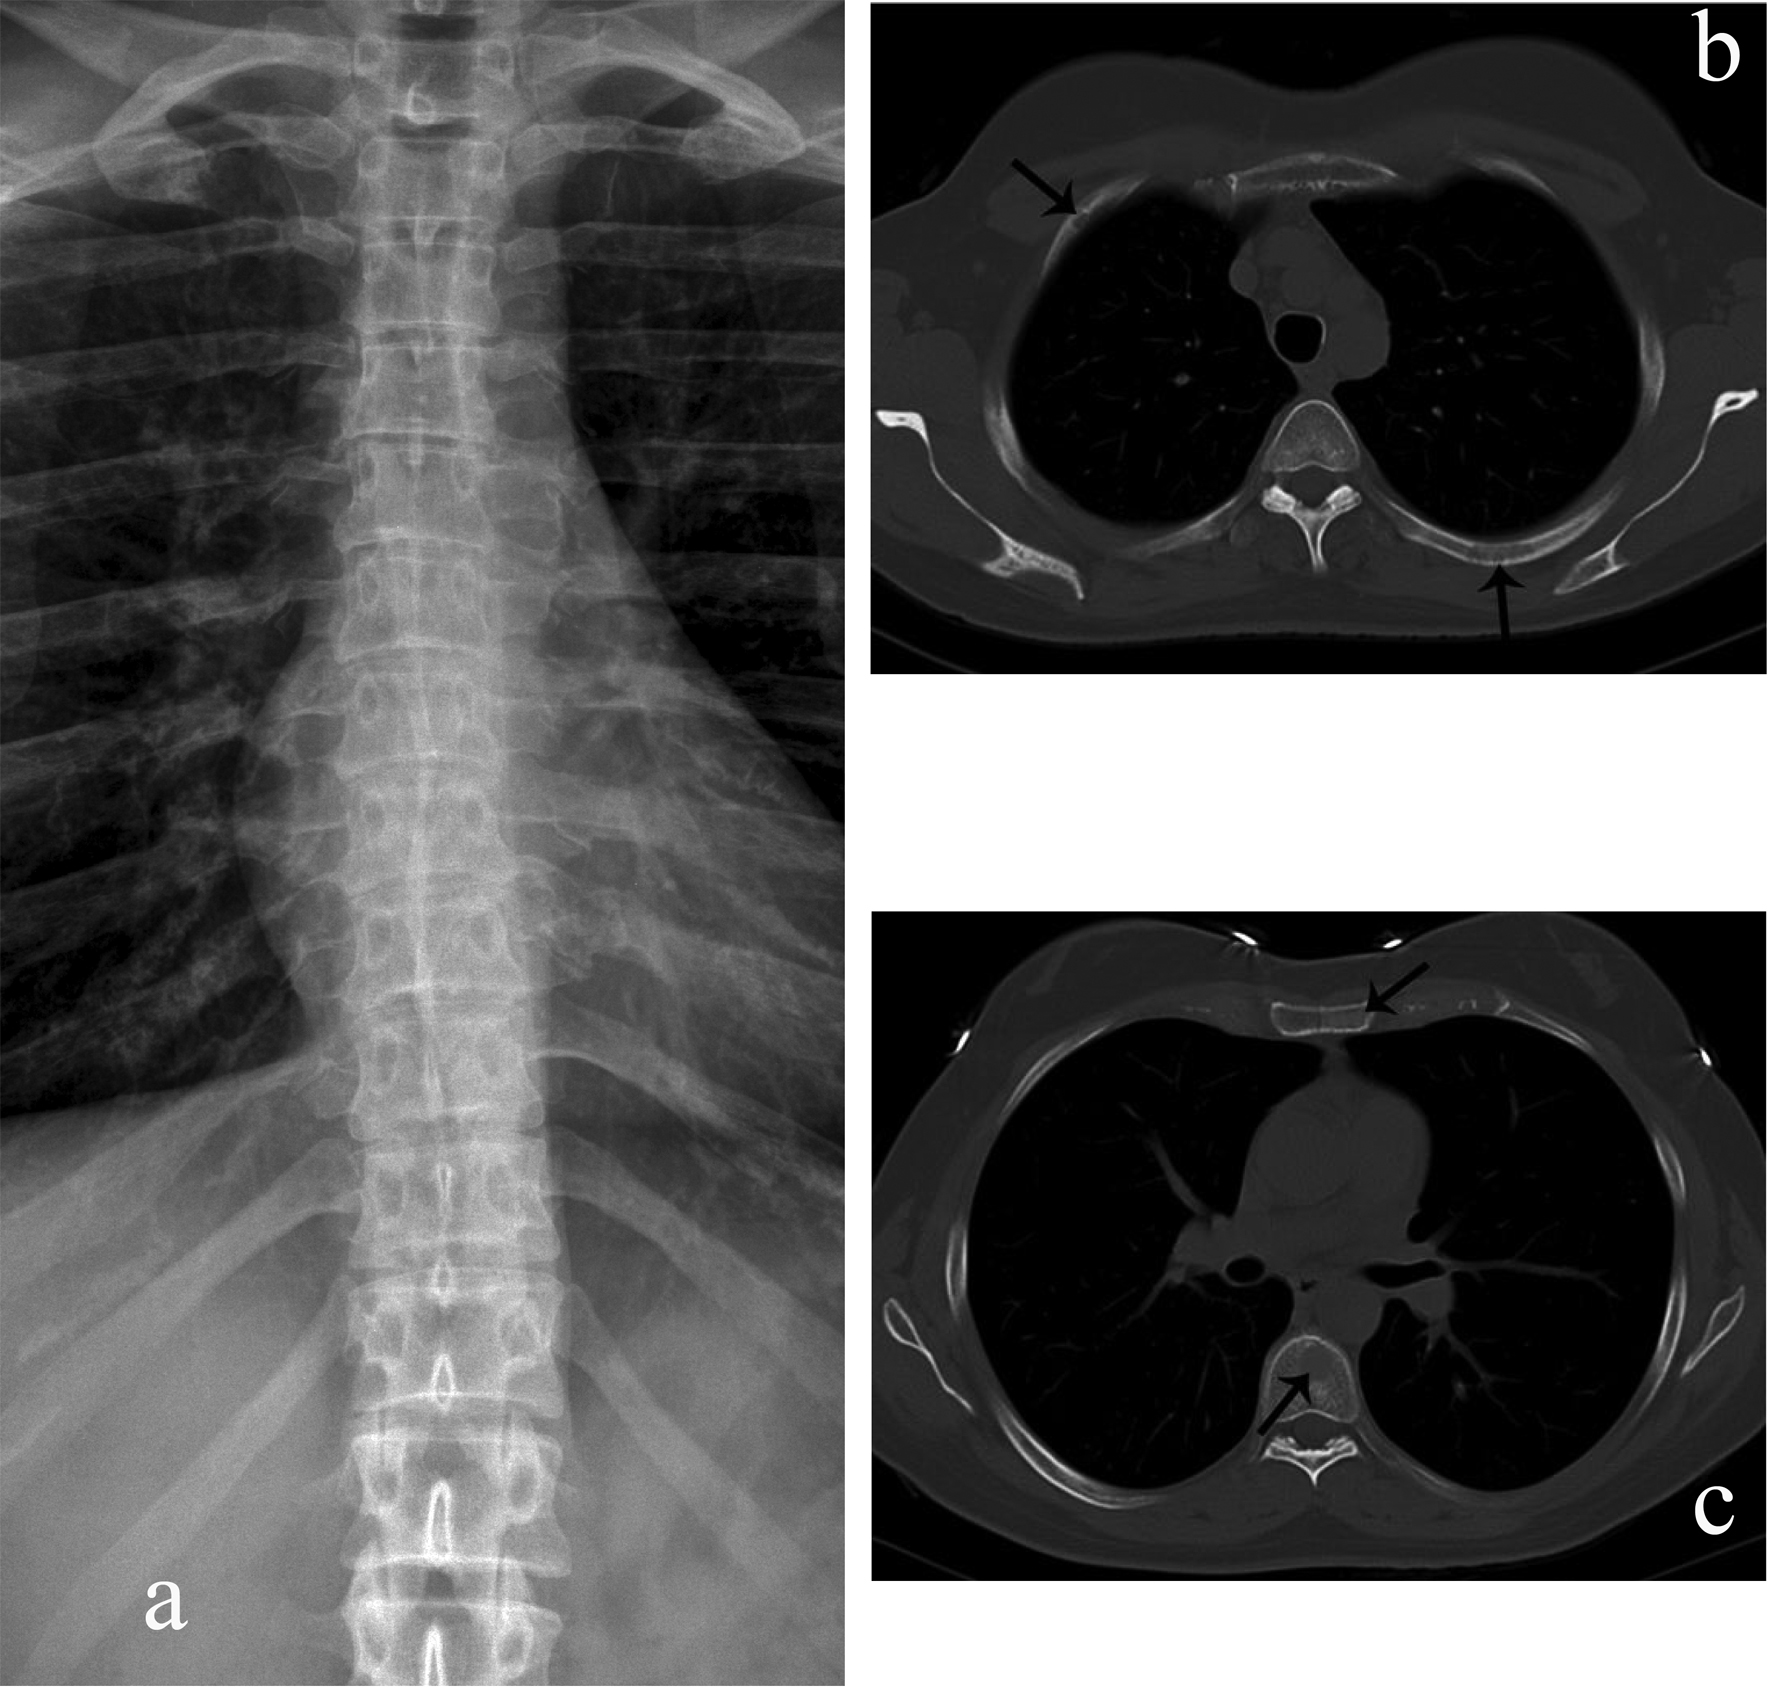

![]() Click for large image | Figure 1. Rib, sternal, and vertebral body myelomatous lesions seen by WBCT (arrows) (b, c) but not conventional skeletal radiography (a). |

Whole body multidetector computed tomography (WBCT) has been shown to be more sensitive in detecting small osteolytic lesions (< 5 mm) in the spine as compared to whole body MRI and 18F-fluorodeoxyglucose positron emission tomography (FDG-PET) [11, 12]. WBCT can detect early small lytic bone lesions in the vertebral bodies, scapulae, ribs and sternum (Fig. 1) and determine the fracture risk better than CSS [21, 22]. In addition, over 30% of trabecular bone loss is needed before lytic bone lesions can be detected by plain films [21, 22]. This is significant because the most common areas of myelomatous bone disease are in the vertebrae, ribs, skull and shoulders [23]. WBCT is faster without a need for repositioning frail patients with bone pain; however, the cost of the WBCT is substantially more than CSS (at our institution WBCT costs $2,822 US dollars in comparison to $607 US dollars for CSS). The slightly higher radiation doses of the WBCT are not usually an issue in a disease that mainly affects the elderly. WBCT is nonspecific for osteopenia or osteoporosis. Although there is a risk of renal insufficiency if intravenous iodinated contrast is used in patients with MM, especially those with Bence-Jones proteinuria, this is not an issue in standard noncontrast WBCT. Also in our study, 2 patients were diagnosed with renal cell carcinoma after the finding of incidental renal masses on WBCT (Fig. 2).